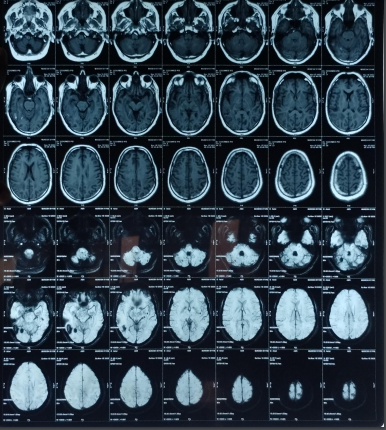

The patient’s routine blood investigations were normal. Serology for HIV, hepatitis B, C, and syphilis was negative. His MRI brain showed a parenchymal bleed in right temporo occipital regions with intra-ventricular leakage of blood and tiny petechial haemorrhage in brain parenchyma bilateral. extensive signal changes in cerebellar hemisphere, bilateral gangliothalamocapsular region, pons, midbrain and deep white matter of both cerebral hemisphere? Microangiopathy? CADASIL.

Early-onset dementia (onset before age 65) is a thought-provoking ailment with many possible causes, including early-onset familial Alzheimer’s disease, frontotemporal lobar degeneration, Parkinson’s dementia, Lewy body dementia, disorders of amino acid and organic acid metabolism, leukodystrophies, lysosomal storage diseases, disorders of metal metabolism, and mitochondrial diseases [6]. In our patient, the history, physical examination, laboratory investigations, and neuroimaging were not suggestive of these causes and prompted the search for a rare etiology. The most common MRI finding associated with CADASIL is basal ganglia and white matter hyperintensities in T2-weighted sequences that start as punctate or nodular foci and then often become confluent, extensive, and usually symmetrical, mainly in the periventricular region, anterior temporal pole, external capsule, the centrum semiovale, and frontal and parietal areas. In our patient, diagnosis was made mainly from MRI findings as seen in fig. 1, 2.

Fig. 1: Tiny petechial hemorrhages are seen in bilateral basal ganglia, white matter of both cerebral hemisphere, midbrain, pns and cerebellum. Diffuse cerebral and cerebellar atrophy is seen with enlarged ventricle due to atrophy. Acute to subacute parenchymal bleed is seen in righttemporo–occipital region. minimal intraventricular leakage of blood is also seen in 4th ventricle